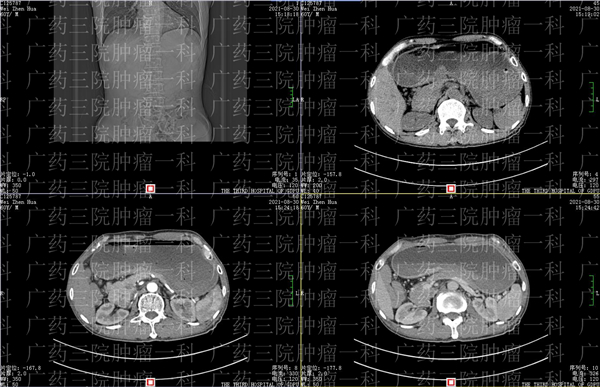

通过增强CT可以看到,韦先生目前病情考虑胃窦部胃癌并周围淋巴结转移,有少量腹水,右肾也有多发结石。查血常规和生化发现,韦先生的血红蛋白测定、红细胞、谷草转氨酶(AST)、谷丙转氨酶(ALT)、白蛋白(ALB)等数据均有异常。

刘跃军教授结合了韦先生的过往治疗史认为,血清铁低及中度贫血多考虑肿瘤导致慢性失血,肝肾功能指标稍高考虑长期服用中草药引起,结合影像,刘教授认为韦先生可能存在幽门梗阻。